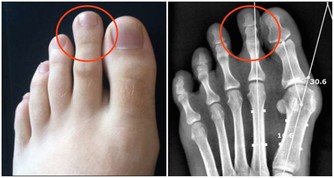

最後運動要因人而異,切不可不服老。年輕人陽氣旺盛,稍多些運動挺好;中老年人陽氣已虛,運動量要低於年輕人。根據個人身體狀況控制好運動量,對於膝蓋受損的人群,千萬不可迷信“每日堅持1萬步”的運動雞湯。